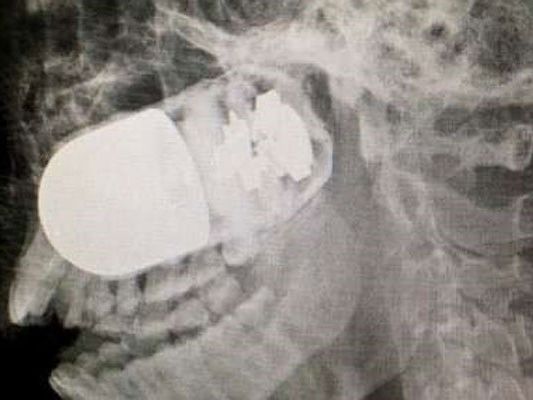

In einer komplizierten Operation haben ko­lumbianische Militärärzte eine scharfe Gra­na­te aus dem Kopf eines Soldaten entfernt. Bei einer Patrouille hatte ein Kamerad ver­seh­­entlich einen Granatwerfer abgefeuert.

Das Geschoss drang auf der rechten unteren Seite in den Schädel des Soldaten ein. Weil ein Transport per Hubschrauber zu gefährlich war, wurde der Soldat in einem Krankenwagen ins Militärkrankenhaus in der Hauptstadt Bogota gebracht, wie die Zeitung “El Tiempo” am Donnerstag berichtete. Die Fahrt dauerte acht Stunden. Weil die Granate zu explodieren drohte, bauten die Ärzte auf dem Parkplatz der Klinik einen improvisierten Operationssaal auf.

Schließlich wurde das Geschoss erfolgreich entfernt. “Es waren fünf entscheidende Minuten”, sagte Chef-Chirurg William Sanchez Maldonado. “Wenn die Granate explodiert wäre, hätte es eine Tragödie gegeben.” Der Zustand des Patienten ist seit der Operation am vergangenen Sonntag stabil. Um das Gesicht des Soldaten wieder herzustellen, sind allerdings noch bis zu vier weitere Operationen notwendig.